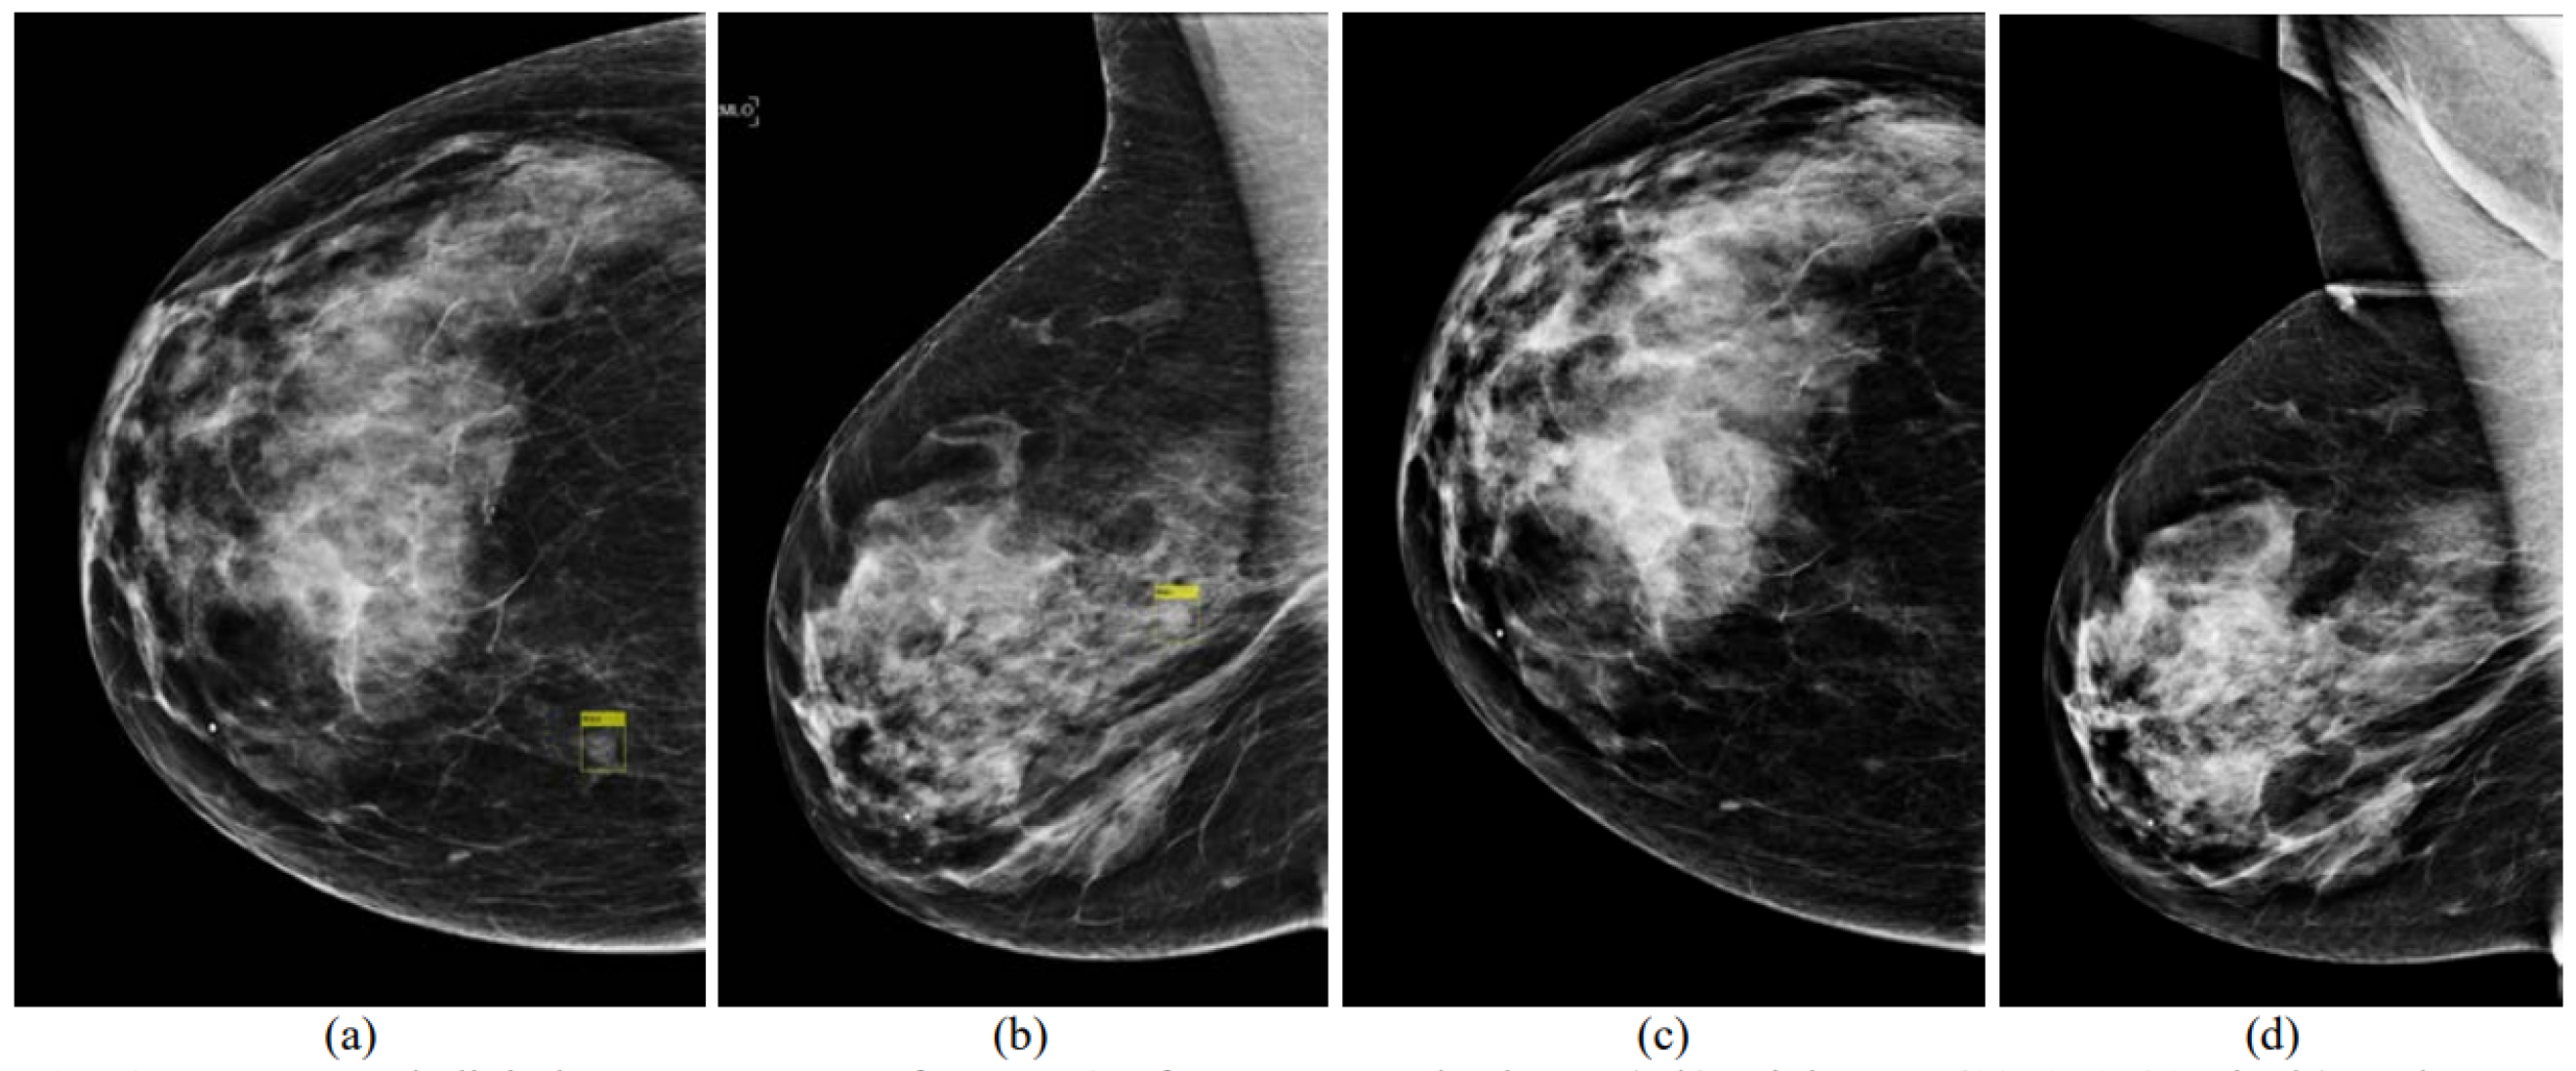

- Loizidou, K.; Skouroumouni, G.; Nikolaou, C.; Pitris, C. An automated breast micro-calcification detection and classification technique using temporal subtraction of mammograms. IEEE Access 2020, 8, 52785–52795. [Google Scholar] [CrossRef]

- Loizidou, K.; Skouroumouni, G.; Pitris, C.; Nikolaou, C. Digital subtraction of temporally sequential mammograms for improved detection and classification of microcalcifications. Eur. Radiol. Exp. 2021, 5, 1–12. [Google Scholar] [CrossRef]

- Loizidou, K.; Skouroumouni, G.; Nikolaou, C.; Pitris, C. Automatic Breast Mass Segmentation and Classification Using Subtraction of Temporally Sequential Digital Mammograms. IEEE J. Transl. Eng. Health Med. 2022, 10, 1–11. [Google Scholar] [CrossRef]

- Loizidou, K.; Skouroumouni, G.; Savvidou, G.; Constantinidou, A.; Nikolaou, C.; Pitris, C. Identification and Classification of Benign and Malignant Masses based on Subtraction of Temporally Sequential Digital Mammograms. In Proceedings of the 2022 44th Annual International Conference of the IEEE Engineering in Medicine & Biology Society (EMBC), Glasgow, UK, 11–15 July 2022; pp. 1667–1670. [Google Scholar]